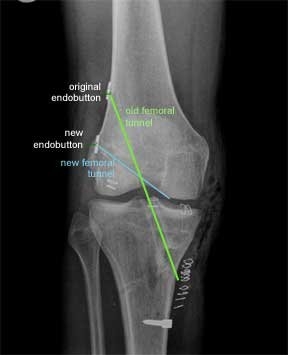

This is an X-ray of a patient who had a trans-tibial ACL reconstruction performed in another hospital. This was revised to a ‘more anatomic’ single bundle ACL, when it failed. The old femoral tunnel is highlighted in green and the new femoral tunnel is highlighted in blue.

This X-ray is from the front as before. The original endobutton was not removed. If you follow the line of the new femoral tunnel it is clear that it has been drilled from an antero- medial portal as the blue line points to two skin clips at this point.

There are further skin clips indicating an antero-lateral arthroscopic portal and a medial proximal tibial incision made to harvest the hamstring graft and drill the tibial tunnel. The larger white implant at the lower end of the tibia is a staple. This is put in for extra support in revision cases. This is in addition to the PEEK screw which was described earlier.